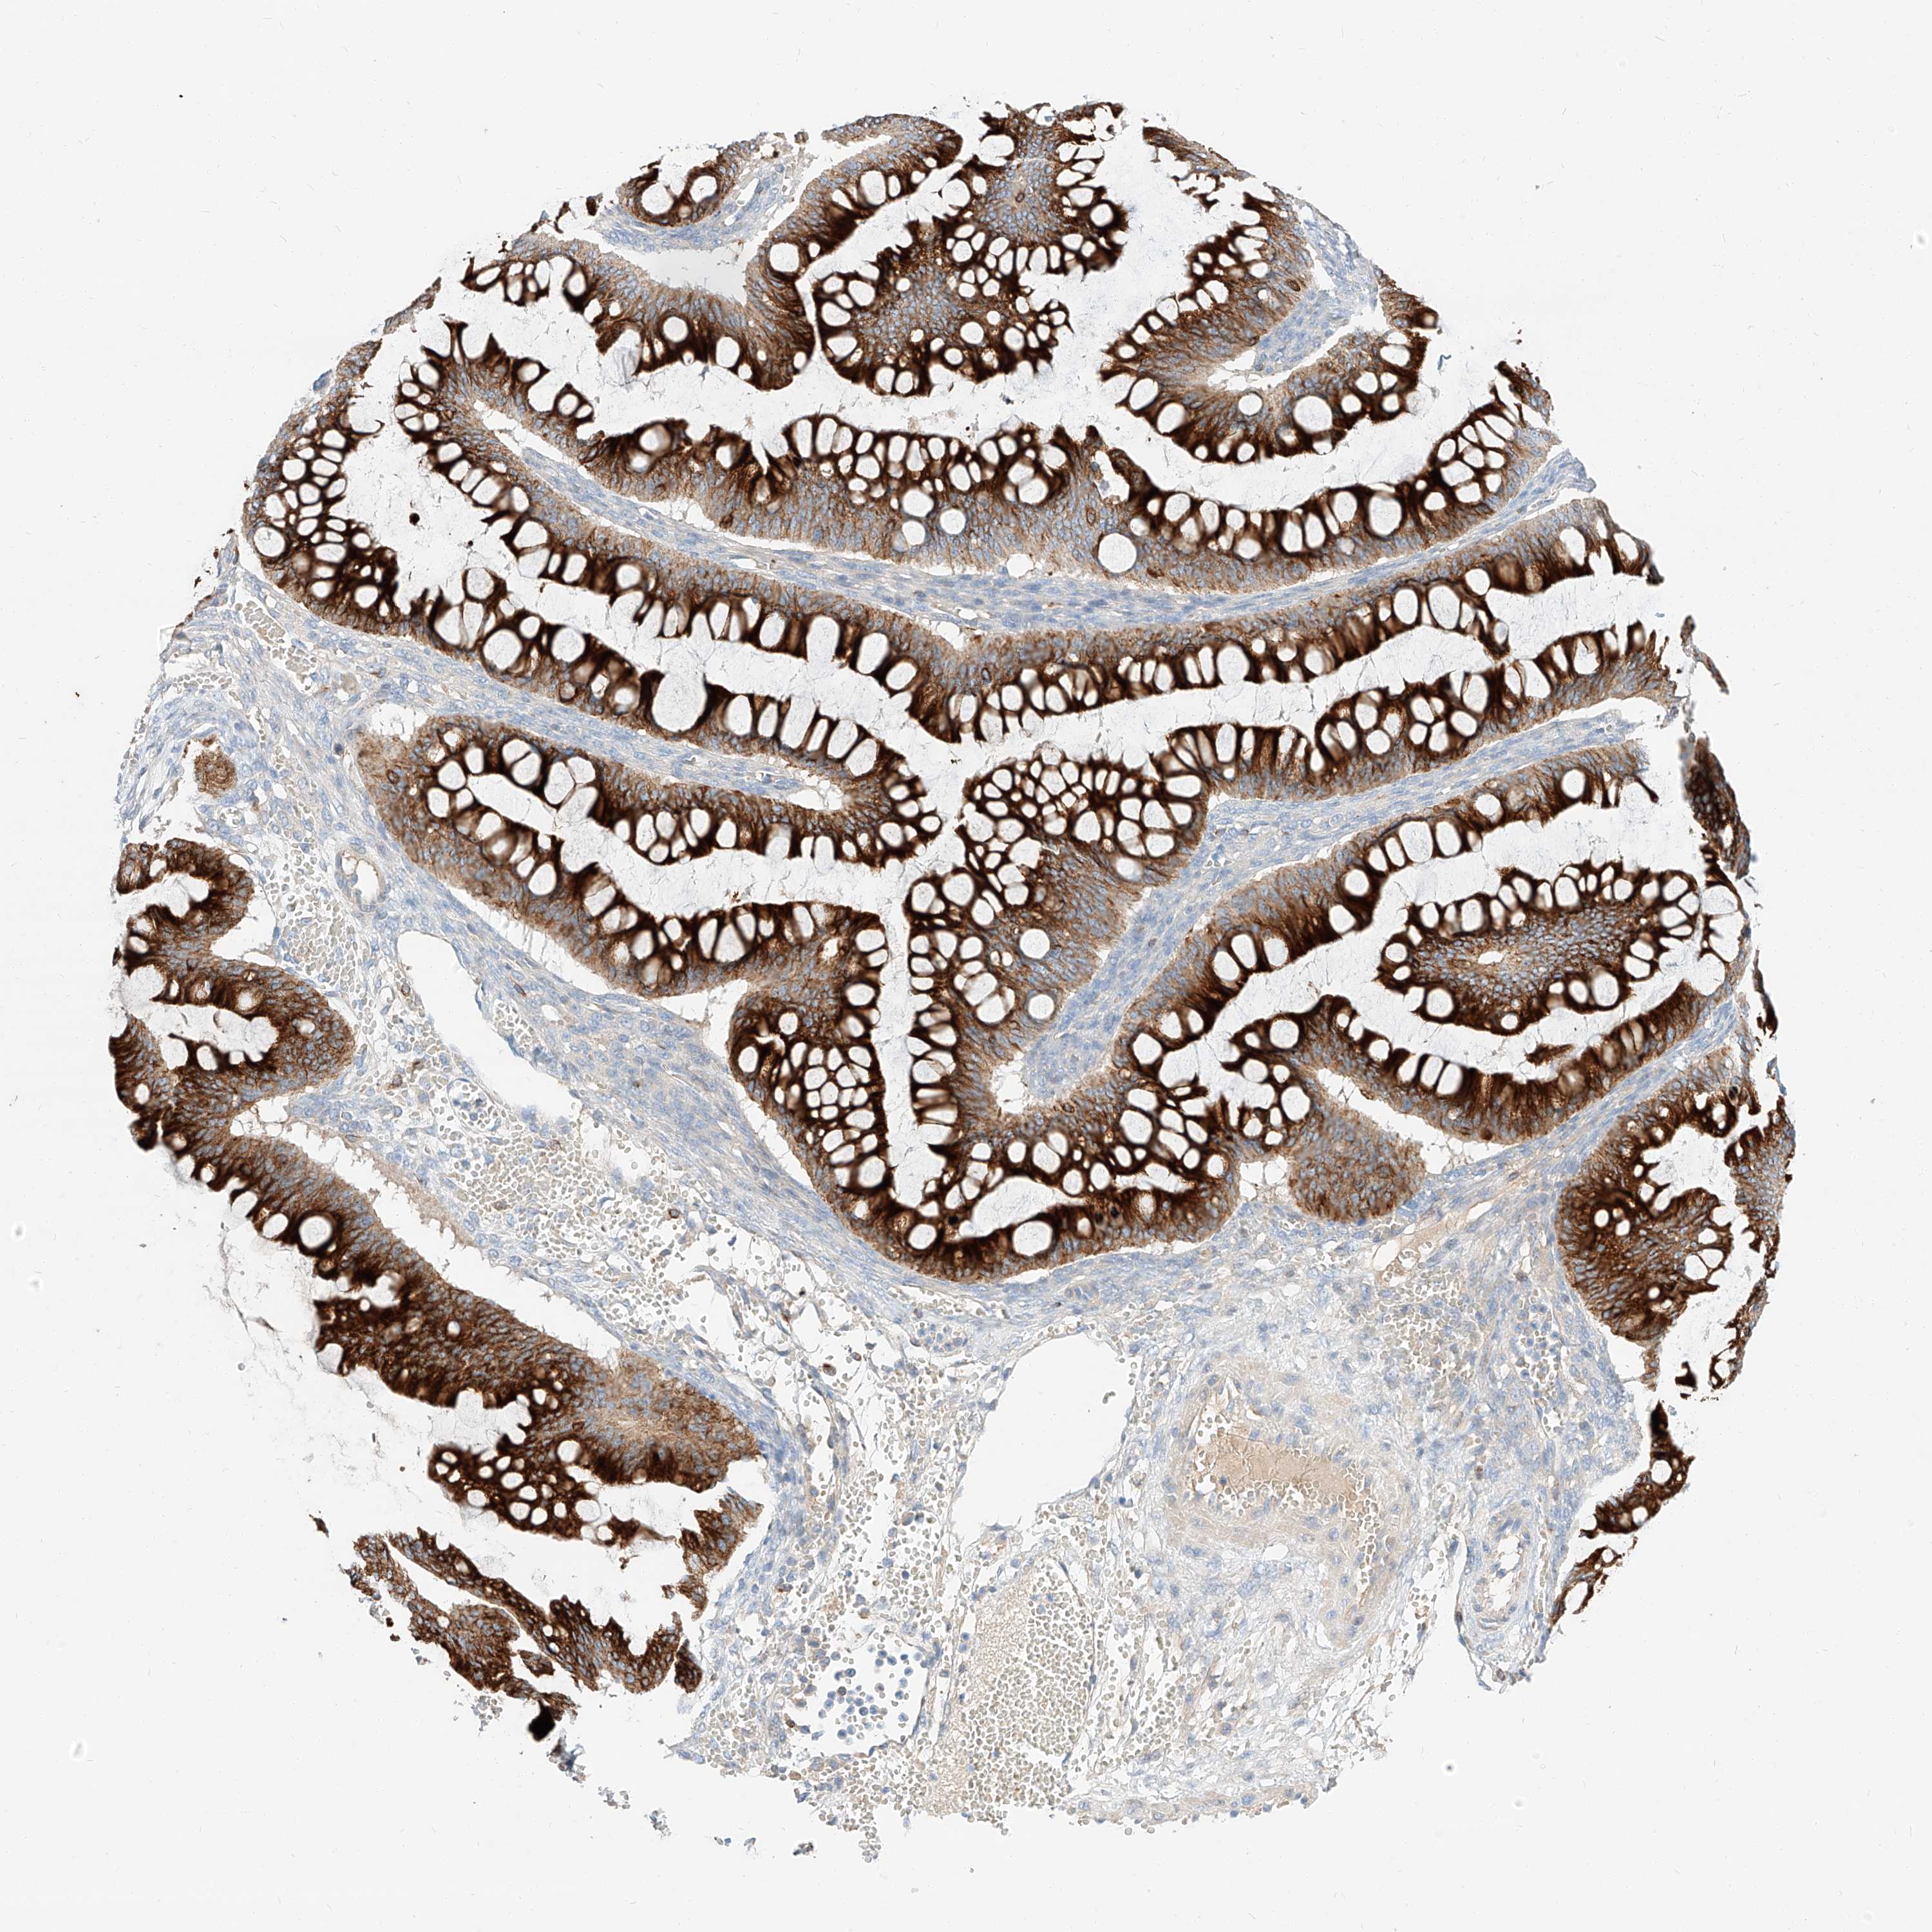

OVARIAN CANCER - Protein expressioni

A mouse-over function shows sample information and annotation data. Click on an image to view it in a full screen mode. Samples can be filtered based on level of antibody staining by selecting one or several of the following categories: high, medium, low and not detected. The assay and annotation is described here.

Note that samples used for immunohistochemistry by the Human Protein Atlas do not correspond to samples in the TCGA dataset.

Antibody stainingi

Antibody staining in the annotated cell types in the current human tissue is reported as not detected, low, medium, or high, based on conventional immunohistochemistry profiling in selected tissues. This score is based on the combination of the staining intensity and fraction of stained cells.

Each image is clickable and will lead to virtual microscopy that enables deeper exploration of all samples and also displays staining intensity scores, fraction scores and subcellular localization as well as patient and tissue information for each sample.

Antibody HPA029712

Antibody HPA029713

Staining

High

Medium

Low

Not detected

Intensity

Strong

Moderate

Weak

Negative

Quantity

>75%

75%-25%

<25%

None

Location

Nuclear

Cytoplasmic/membranous

Cytoplasmic/membranous,nuclear

Cystadenocarcinoma, serous, NOS

Carcinoma, endometroid

Cystadenocarcinoma, mucinous, NOS

Carcinoma, NOS